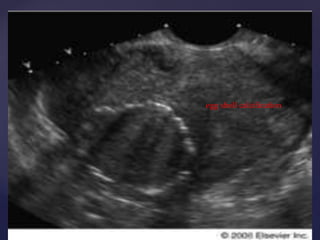

tvs

 Clinically, thediagnosis of uterine myomas is usually confirmed by physical examination. Upon palpation, an enlarged, firm, irregular uterus may be felt.  The three conditions that commonly enter into the differential diagnosis include pregnancy, adenomyosis, and an ovarian neoplasm.  The discrimination between large ovarian tumors and myomatous uteri may be difficult on physical examination, because the extension of myomas laterally may make palpation of normal ovaries impossible during the pelvic examination.  The mobility of the pelvic mass and whether the mass moves independently or as part of the uterus may be helpful diagnostically.